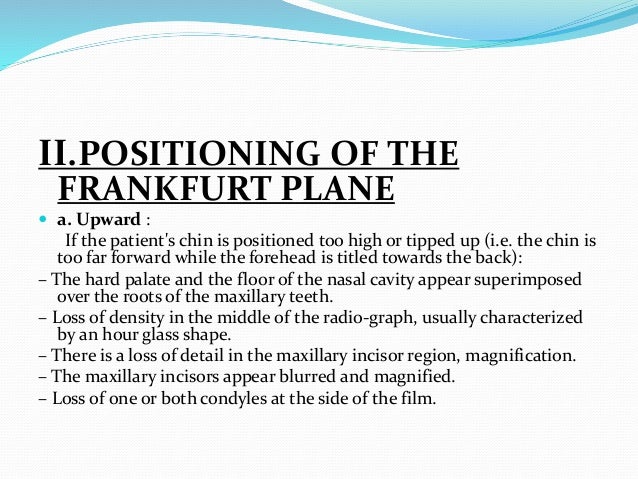

Tragus of the ear must be aligned with the plastic guides ala tragus line should be 50 from level positioning the patient position the patient panoramic lead apron must be used position apron high in front to protect the thyroid apron should be lower in back to expose the neck. Discussion most panoramic x ray machines use the ala tragus line for patient positioning whereas a few use the orbito meatal line. Ala tragus line is one of the common extra oral soft tissue land mark utilized in dental clinics for occlusal plane orientation. Here the occlusal plane should be mildly curved upward to make a smile like line.

The cone film distance used was 5 feet. If the tragus is positioned above the tragus the hard palate will appear as a thick opaque horizontal opacity above over the apices of the maxillary anterior teeth and premolars. Download pdf 1mb sizes 0 downloads 9 views.